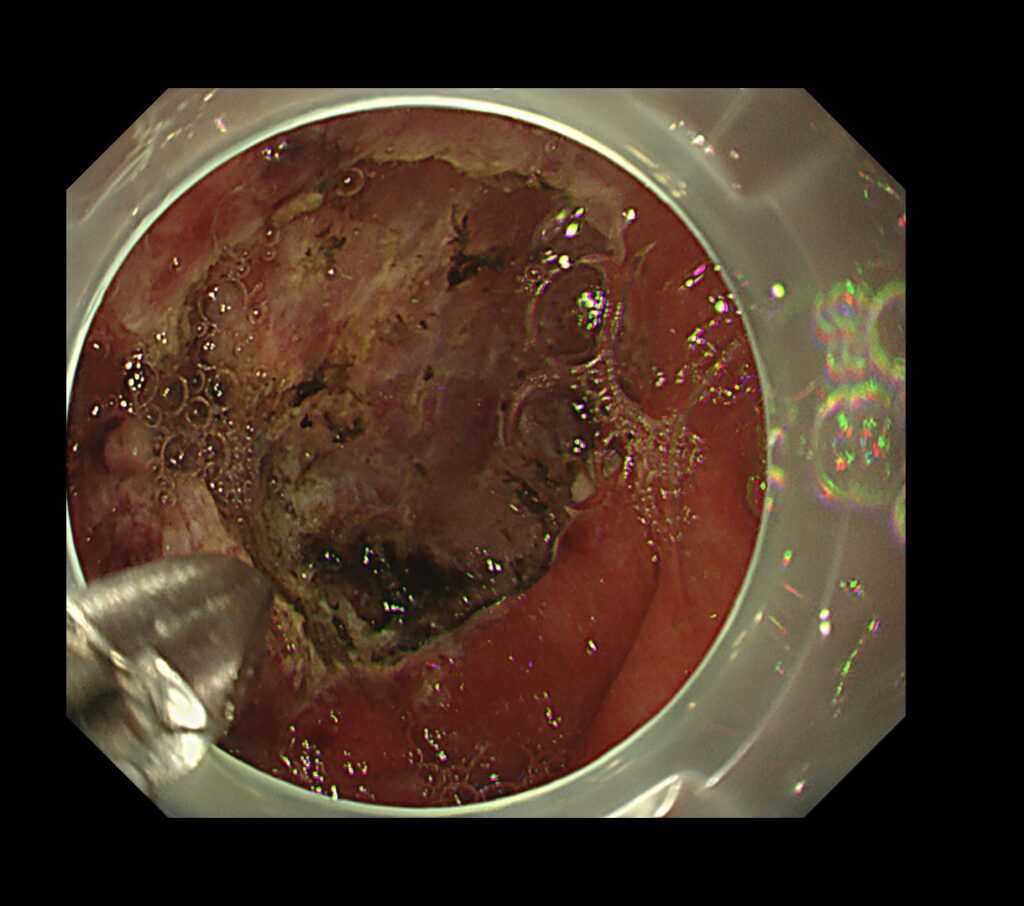

約30分で胃がんの切除完了しております。

当院では、牽引クリップを独自で作り、病変にトラクションをかけることで、病変を切除可能な状態にもっていくテクニックを行っております。

瘢痕症例は、だいたい30分以内に切除完了します。

※このトラクションデバイスは、もともと既成の商品はありますが、値段が高いので、当院では自分たちで作っています。